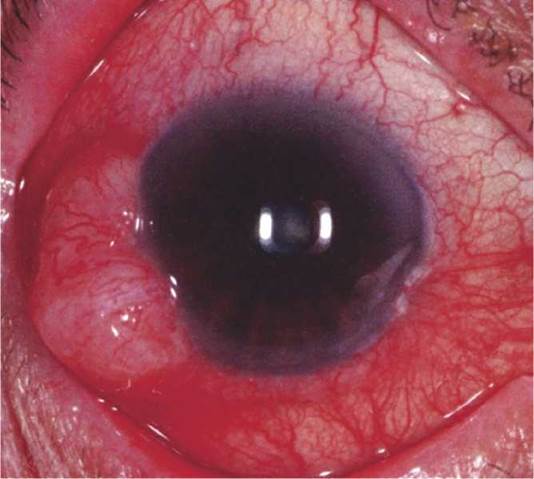

Critical. Unilateral brown or translucent iris mass lesion exhibiting slow growth. It is more common in the inferior half of the iris and in light-skinned individuals. Rare in blacks (see Figure 5.13.1).

FIGURE 5.13.1 Iris melanoma.

Other. A localized melanoma is usually >3 mm in diameter at the base and >1 mm in depth with a variable prominent feeder vessel. Can produce a sector cortical cataract, ectropion iridis, spontaneous hyphema, seeding of tumor cells into the anterior chamber, or direct invasion of tumor into the trabecular meshwork and secondary glaucoma. A diffuse melanoma causes progressive darkening of the involved iris, loss of iris crypts, and increased IOP. Focal iris nodules can be present.